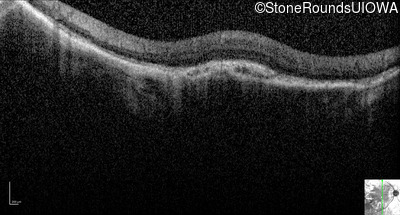

Optical Coherence Tomography - Right - 20/200 +1

Exemplar / OCT Stack

OCT Stack